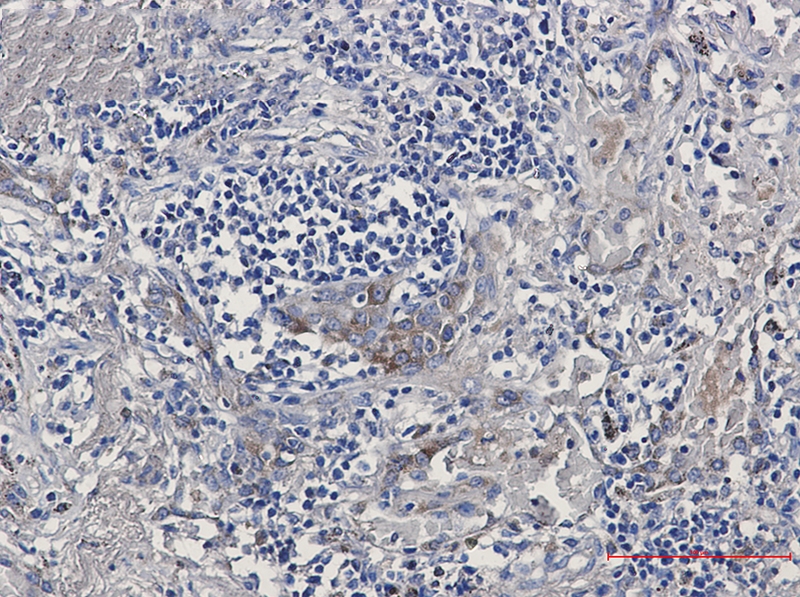

Immunohistochemistry of ARTS1 in paraffin-embedded Human lung cancer tissue using ARTS1 Rabbit mAb at dilution 1/50